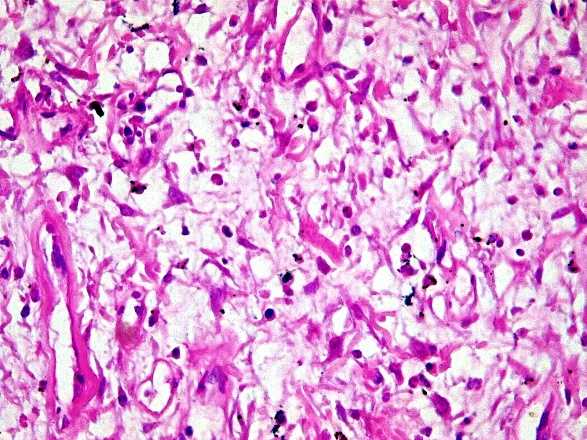

Histological examination revealed sparse cellular areas. These were short bundles of spindle cells concentrically wrapped around capillaries. The chorion was rather loosely edematous and fibromyxoid. There were hemorrhagic changes and a marked polymorphic inflammatory infiltrate with numerous eosinophilic polynuclear. The contralateral mucosa was regular and partially abraded. The lesion was poorly circumscribed, unencapsulated, and developed at the expense of the submucosa, suppressing the muscularis mucosae and muscularis (Figure 1).

Figure 1. (a) Macroscopic view of a voluminous, pedunculated polyp in the small intestine measuring 9 cm in length, which is obstructing the intestinal lumen. (b) G50 microscopy with HE staining showing an intestinal wall in which the submucosa is the site of sparsely dense spindle cell patches within a loose fibro myxoid chorion with hemorrhagic remodeling and a polymorphic inflammatory infiltrate. G200 and G400 microscopy with HE staining better show cellular detail (c and d).